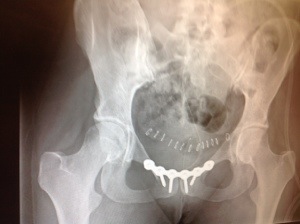

- The two days shy of eight months BEFORE the surgery that repaired my diastasis symphysis pubis sustained in childbirth was far and away the hardest time. I’m not going to dwell on that now.

- Then there was surgery and the time I spent in the wheelchair. Blue Sunshine taught me a lot — about myself, about my family and friends and about the good in strangers. It was just before surgery that I began writing this blog. Because of that I have met new people, some who are going through DSP, others aren’t but offer moral support as fellow new moms. Thank you all for your support and care. I think of you often and wish you all strength and wellness.